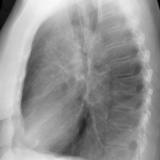

RLL collapse 4 Lat

Date: 03/02/2006

Views: 3274